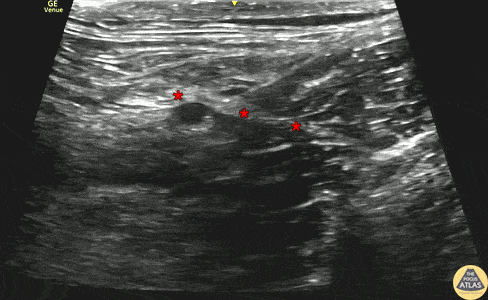

70s F presented with lower extremity pain after a mechanical trip and fall on the stairs. She arrived with a closed deformity of the distal thigh, and radiographs confirmed a comminuted distal femur fracture. A fascia iliaca block was performed for analgesia and to facilitate traction pinning. The block is shown here, with the needle entering from the lateral aspect (screen right) and depositing anesthetic just deep to the fascia iliaca (*) which lies deep to the sartorius muscle and superficial to the iliacus muscle. The patient had significant relief soon after the block and was able to be admitted for surgery. Dr. Michael Heffler, PGY3, Dr. Spencer Tomberg, Attending Denver Health Residency in Emergency Medicine